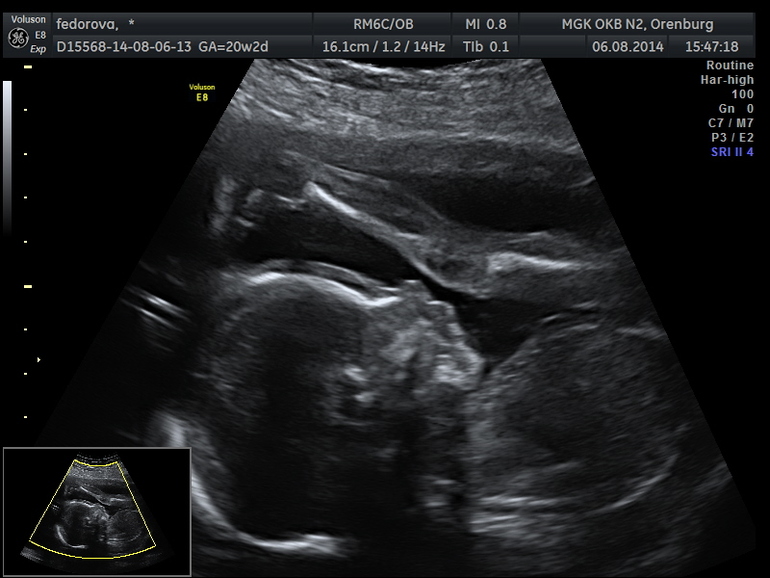

Не выдержала и через неделю записалась в медико-генетическую консультацию.К очень хорошему врачу. По результатам ребенок на 21-22 недели. У нас мальчик. Очень хотелось девочку, сначала беременности была уверенность, что именно деваха. Но мы предполагаем, как говориться. Будем рады и сыночку. Не смогла увидеть мою шейку.Пришлось смотреть вагинально. И вот какая то неразбериха. В жк намерили абдоминально 38, через неделю вагинально 26. Какие интересно прогнозы????

И вот наш масик